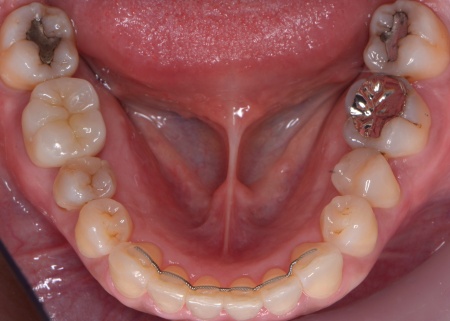

さらに、下顎の内側には下顎隆起(かがくりゅうき)という骨の出っ張りが見られました。

これは、強く噛む力が長期間かかることで骨が発達して発生するものなので、奥歯への過度な負担を示しています。

6ヶ月後、歯周組織の回復を確認し、上下すべての歯を対象とした矯正治療を開始します。

矯正方法としては、上下の歯全体の表面にブラケットと呼ばれるボタン状の装置を接着し、そこにワイヤーを通して歯を動かすマルチブラケット装置を採用しました。

マルチブラケット装置で矯正治療中です。

下顎隆起を除去しました。